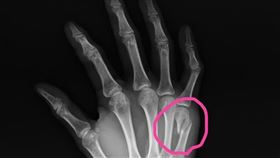

林郁婷奪金 國中生激動捶牆竟拳擊手骨折

「台灣拳后」林郁婷成功奪下巴黎奧運57公斤女子拳擊金...

氣到捶牆竟得「拳擊手骨折?」醫解惑

林口長庚醫院兒科急診主治醫師吳昌騰指出,一位十幾歲的...